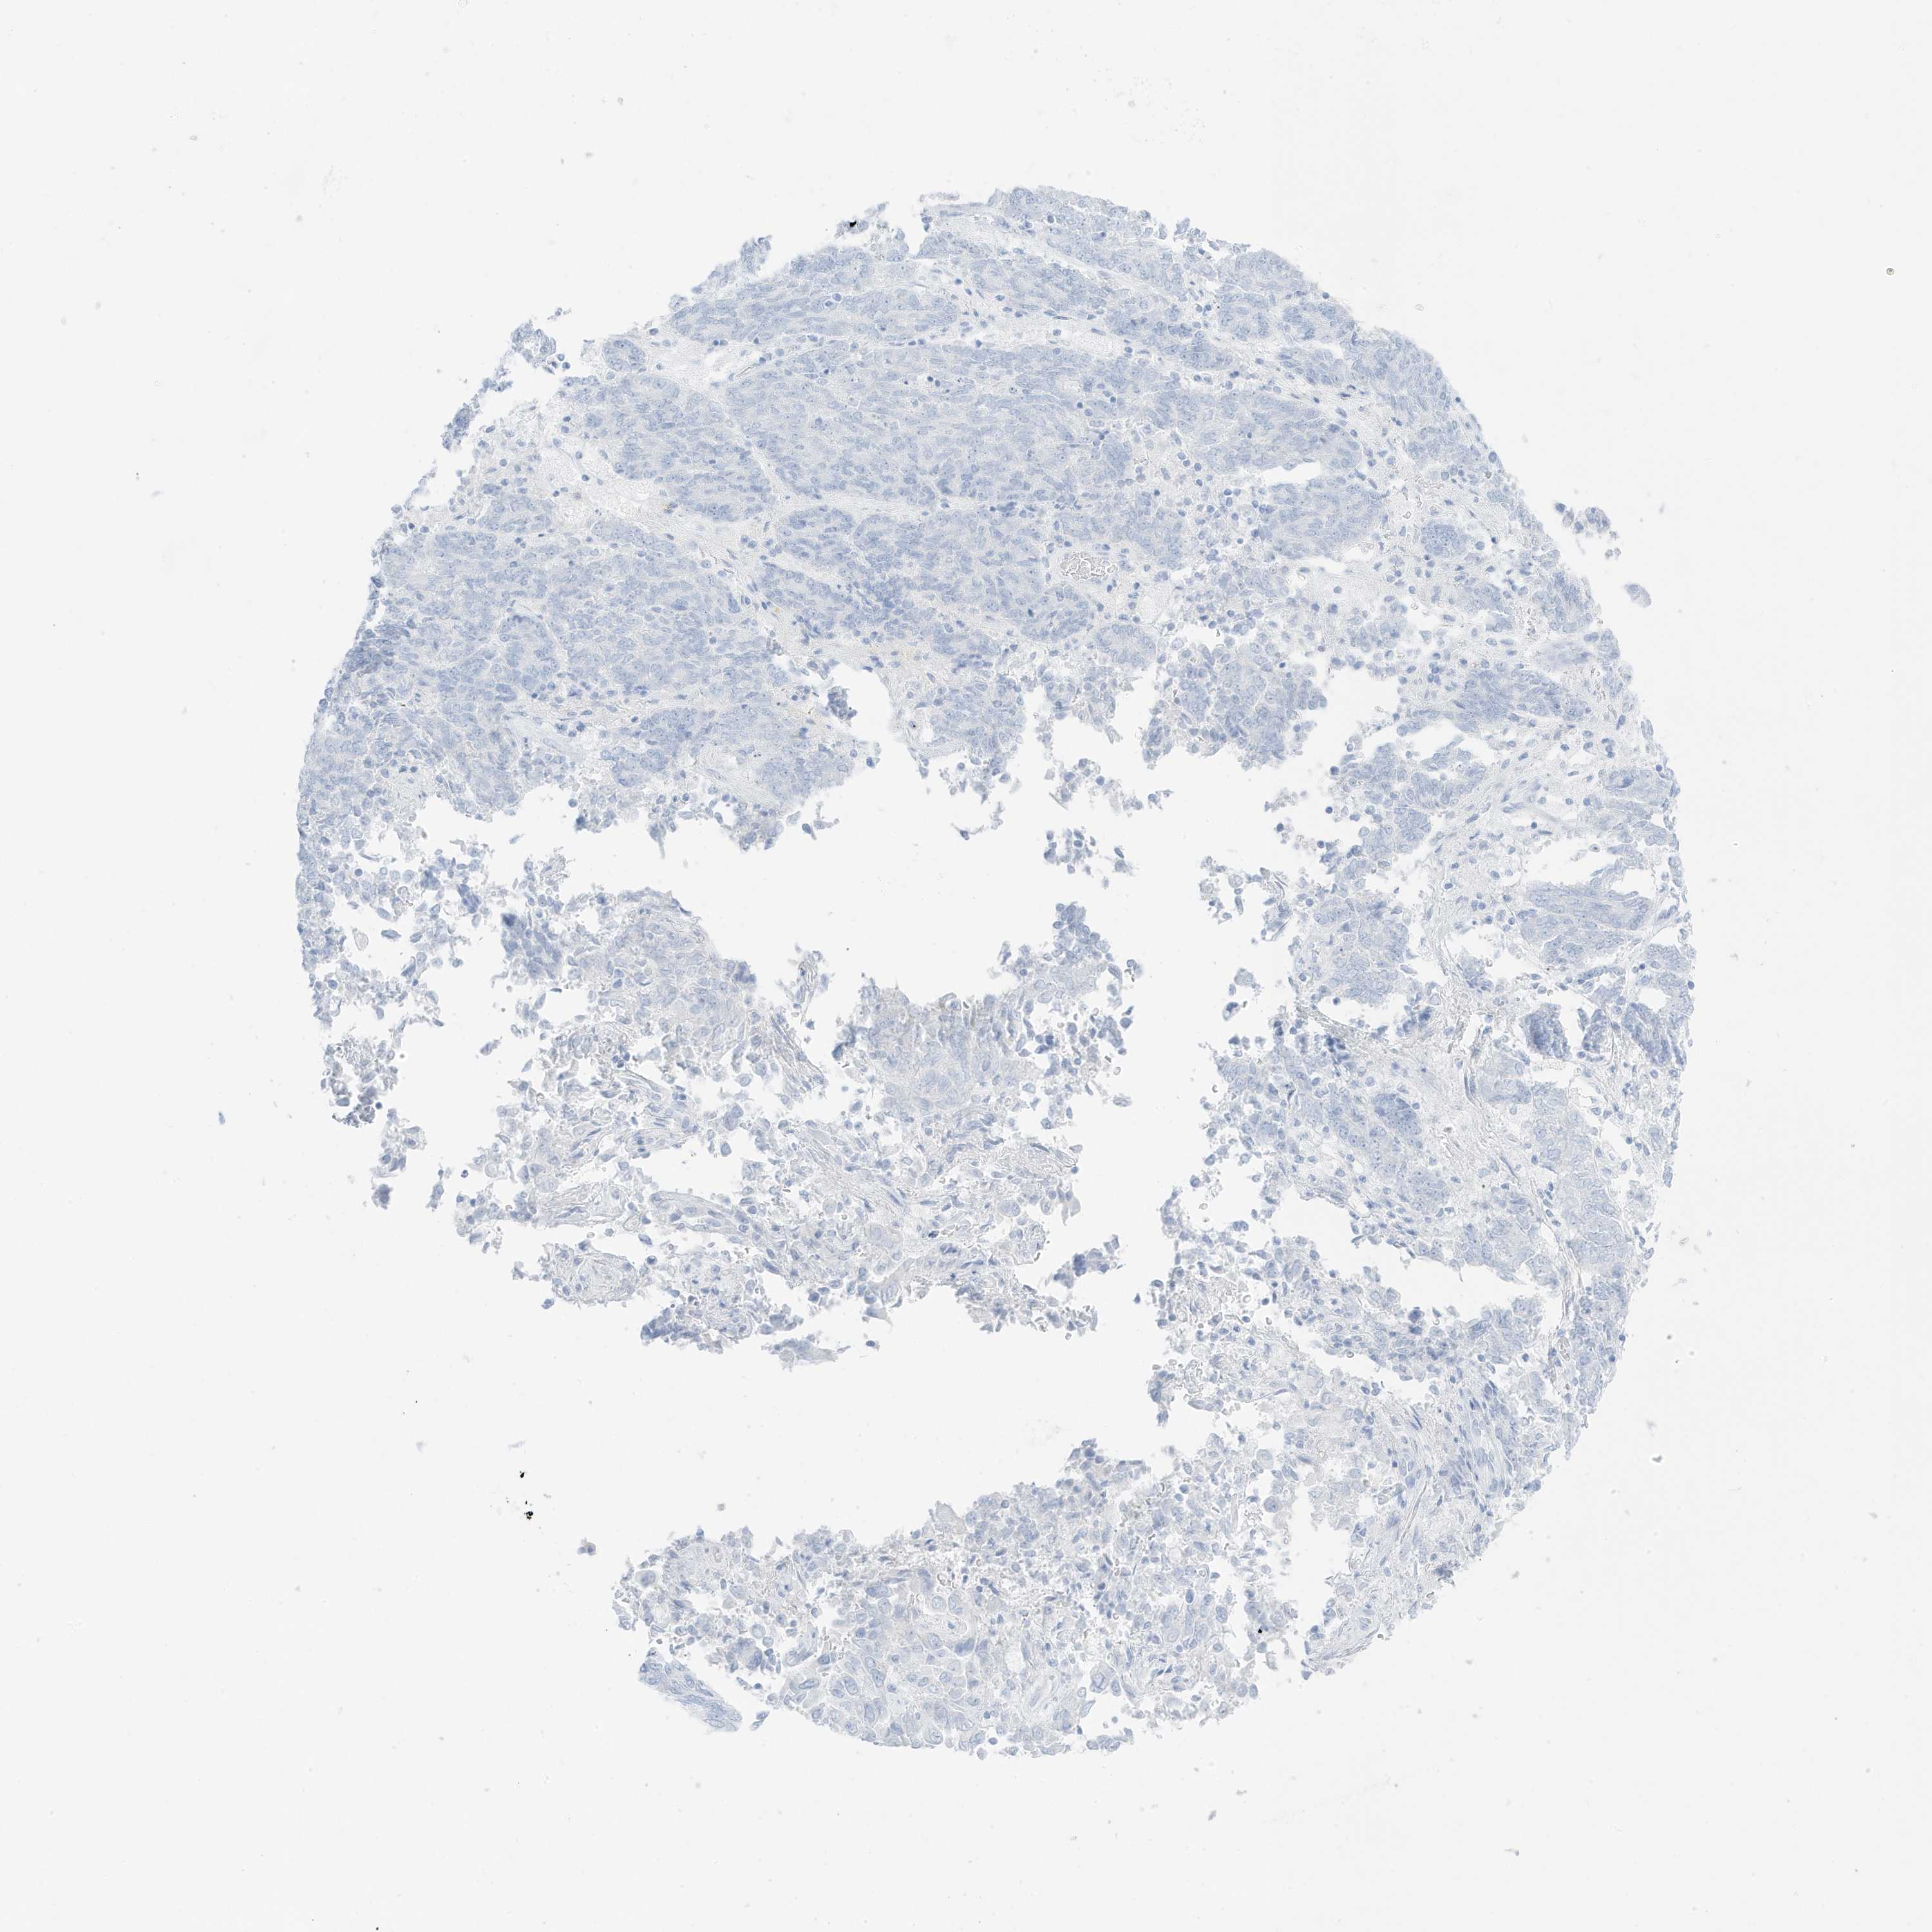

ENDOMETRIAL CANCER - Protein expressioni

A mouse-over function shows sample information and annotation data. Click on an image to view it in a full screen mode. Samples can be filtered based on level of antibody staining by selecting one or several of the following categories: high, medium, low and not detected. The assay and annotation is described here.

Note that samples used for immunohistochemistry by the Human Protein Atlas do not correspond to samples in the TCGA dataset.

Antibody stainingi

Antibody staining in the annotated cell types in the current human tissue is reported as not detected, low, medium, or high, based on conventional immunohistochemistry profiling in selected tissues. This score is based on the combination of the staining intensity and fraction of stained cells.

Each image is clickable and will lead to virtual microscopy that enables deeper exploration of all samples and also displays staining intensity scores, fraction scores and subcellular localization as well as patient and tissue information for each sample.

Antibody HPA035603

Antibody HPA035962

Staining

High

Medium

Low

Not detected

Intensity

Strong

Moderate

Weak

Negative

Quantity

>75%

75%-25%

<25%

None

Location

Nuclear

Cytoplasmic/membranous

Cytoplasmic/membranous,nuclear

Adenocarcinoma, NOS

Adenocarcinoma, metastatic, NOS